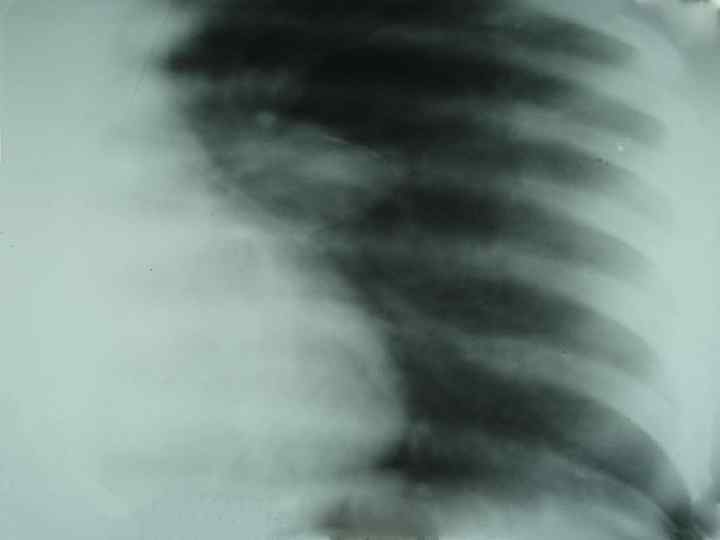

Осложнения локальных форм первичного туберкулеза n n n n туберкулез бронхов; плеврит; ателектаз; бронхо-легочные поражения; диссеминация; первичная каверна; казеозная пневмония; хроническое течение.

Первичный туберкулезный комплекс n Стадии патологоанатомической (рентгенологической) динамики: пневмоническая, n рассасывания (биполярности), n уплотнения, n кальцинации (формирование очага Гона). n

Первичный туберкулезный комплекс (стадия рассасывания) n Рентгенологическая картина: определяется фокусная тень связанная дорожкой с расширенным корнем (легочный аффект + лимфангоит +лимфоаденит).